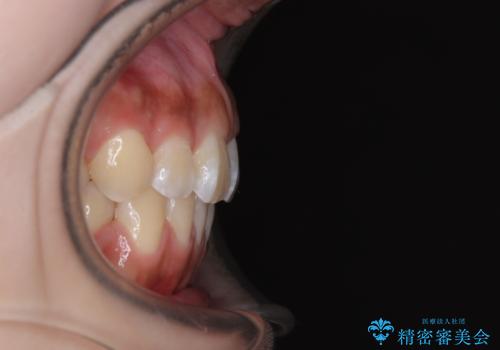

- 口元から飛び出てしまう前歯を気にして来院された患者様です。

上下前歯が嘴のように前方に突出しており、唇が閉じにくい状態であったため、上下左右の第一小臼歯4本を抜歯して、口元の突出感を改善することとしました。

口元の印象が劇的に解消され、気にしていたガミースマイルも図らずも改善することができました。